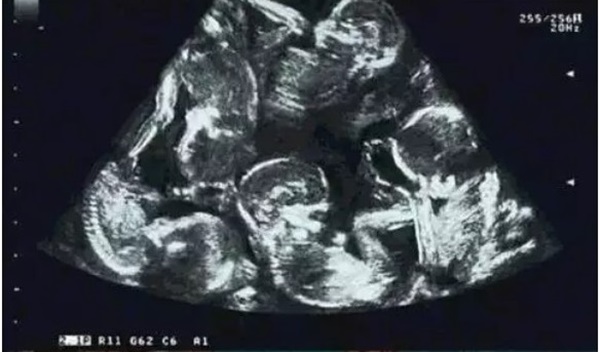

Hình ảnh siêu âm cho thấy chị Alexandra mang thai 5.

Tuy nhiên, vào tháng thứ 3 của thai kỳ, bác sĩ thông báo chị Alexandra có 4 em bé chứ không phải 2. Bà mẹ hạnh phúc nói: "Ban đầu, bác sĩ báo tôi mang thai đôi, nhưng đến tháng thứ 3, bác sĩ phát hiện ra rằng có 4 em bé bên trong cái bụng khổng lồ của tôi. Tuy nhiên, qua tháng thứ 5, mọi người đều sững sờ khi nhìn hình ảnh siêu âm. Có tất cả 5 đứa trẻ ở đó".